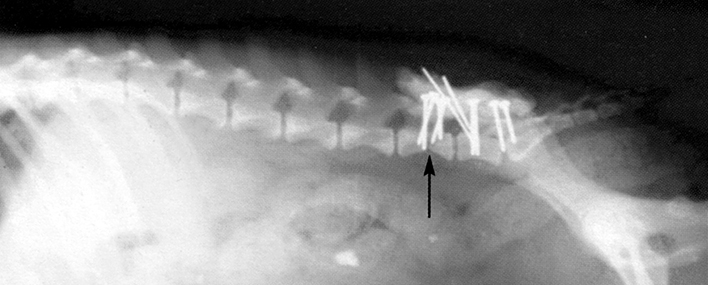

Заболевания позвоночника у домашних животных: диагностика и лечение

Раздел: Визуальные истории